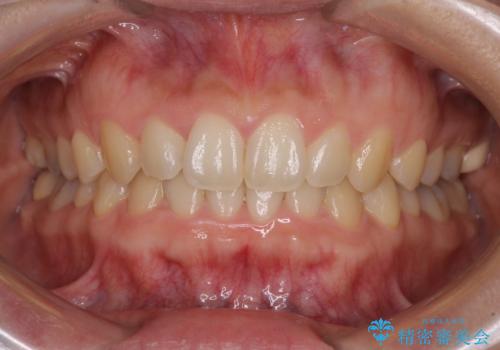

毎日しっかりと装着してくださったので、概ねシミュレーション通りに歯を移動させることができました。

治療前には接触することのなかった上下の前歯が接触するようになり、食事の際前歯でものをかみ切れるようになりました。

気にしていた口元の印象が改善され、患者様には大変満足していただきました。